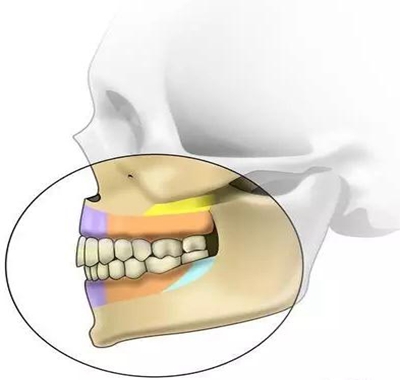

根據(jù)骨類型,骨密度,牙根間距、粘膜厚度不同,把上下頜分為不同區(qū)域,分別用紫橙藍黃四種顏色標記,這些區(qū)域就是傳統(tǒng)的可植入部位,每個部位所選擇的支抗釘也相應會有所差異